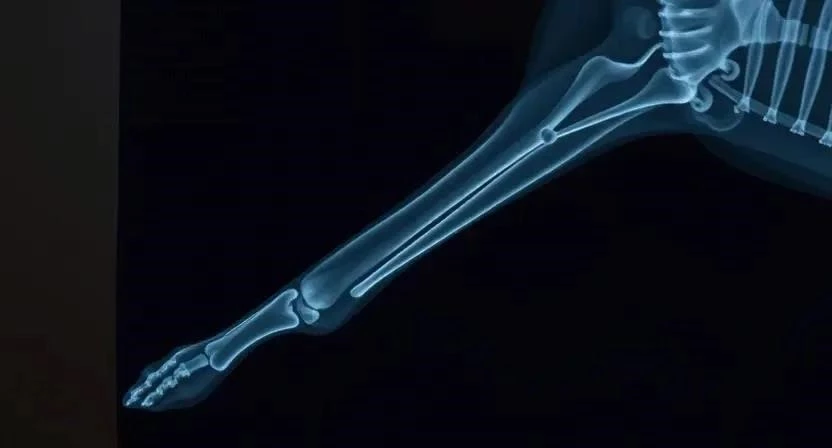

Рентгенологическое исследование

Рентген – это метод диагностики, основанный на использовании рентгеновских лучей. Рентген позволяет выявить переломы костей, инородные тела, опухоли и другие патологии. Рентген может быть противопоказан беременным собакам.